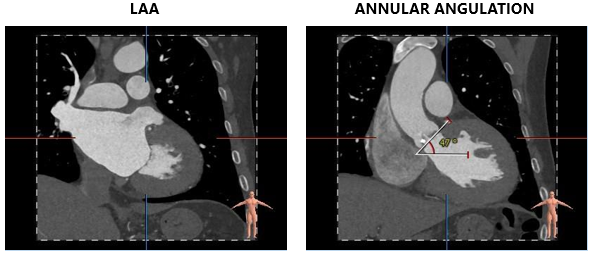

术前CT评估

主动脉根部测量

CT特点:三叶式主动脉瓣,瓣叶轻度钙化,钙化主要位于无窦瓣叶边缘及左右窦交界处,瓣叶显著增厚伴左右窦部分融合;瓦氏窦、窦管交界内径偏小,升主动脉内径可;右冠开口高度可,左冠偏低,瓣叶冗长;非横位心。

瓣上测量

瓣上测量:瓣叶钙化较轻、增厚显著,瓣膜锚定难度稍高;左右窦交界纤维性融合存在一定限制。